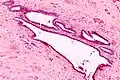

It is characterized by cysts with tubal-type epithelium (e.g. ciliated epithelium) surrounded by a fibrous stroma. It is not often associated with hemorrhage.

Intermed. mag. -